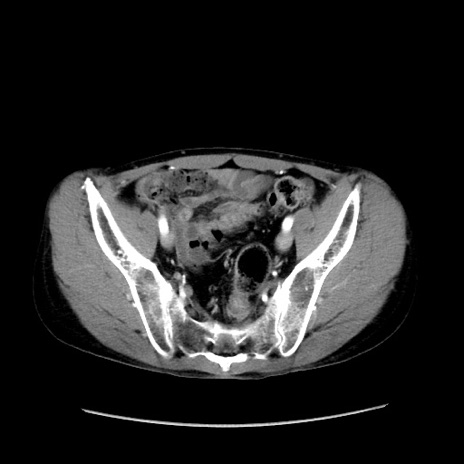

症例37(横断像)

【症例】40歳代 男性

【主訴】腹痛

【現病歴】4時間ほど前に電車に乗車中に臍部上より腹痛出現。徐々に増悪し起立困難となり、救急外来受診。生ものは数日食べていない。今朝お雑煮を食べた。

【身体所見】BT 36.8℃、BP 117/84mmHg、HR 91/min、SpO2 97%、苦悶様、腹部:臍上部広範囲圧痛あり、反跳痛±

【データ】WBC 8100、CRP 0.03